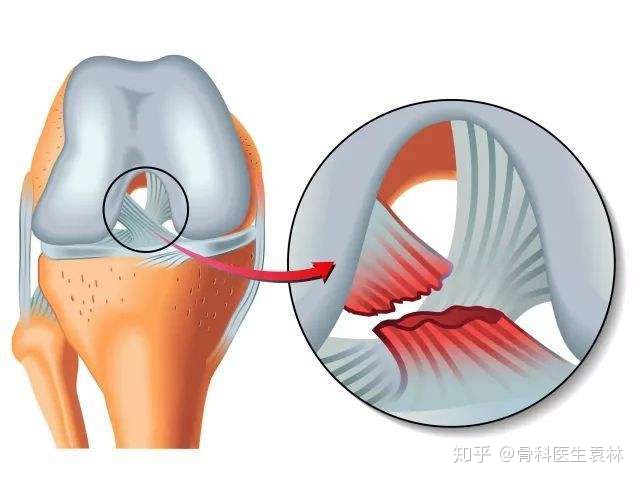

前十字韧带

膝关节十字韧带又称交叉韧带,位于股骨内外髁之间,前后两条,互相交叉。前十字韧带,位于膝关节内,连接股骨与胫骨(起于股骨髁间窝外后部,向前、内、下止于胫骨棘前侧),主要作用是限制胫骨向前过度移位。后十字韧带

前十字韧带损伤

膝关节过伸或过度外翻可引起膝关节前十字韧带损伤。如为过度外翻引起,可同时发生内侧付韧带断裂。前十字韧带损伤合并内侧半月板损伤也较常见。后十字韧带损伤